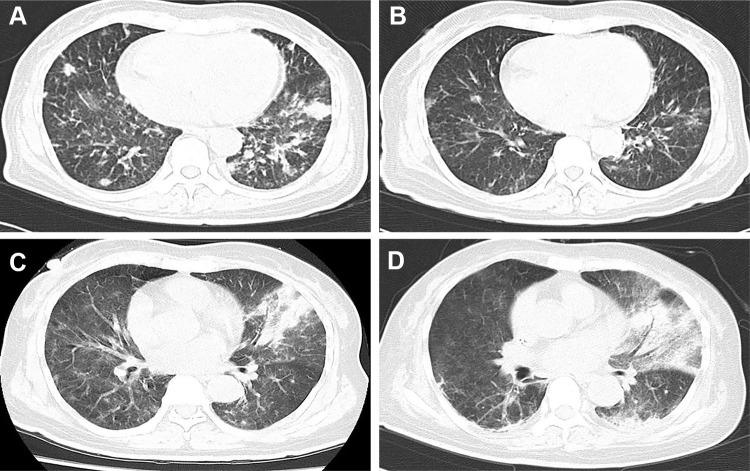

Monocytopenia and mycobacterial infection (MonoMAC) syndrome is a rare disease. Herein, we reported a 65-year-old Asian woman, previously diagnosed with myelodysplastic syndrome (MDS), suffering from recurrent pneumonia, intermittent fever, fatigue, and chest tightness lasting for five months. She was ultimately diagnosed with MonoMAC syndrome with () infection and GATA2 mutation through metagenomic generation sequencing (mNGS) of peripheral blood specimen, for which she was given anti-NTM therapy. Her situation significantly improved within 2 weeks of therapy. We discussed the clinical features, genetic characteristic, and prognosis of this disorder, aiming to further elucidate this rare syndrome. For MDS/AML patient with recurrent mixed infection and pancytopenia (especially with monocyte absence), MonoMAC syndrome should be highly suspected, and germline mutation and pathogen sequencing should be performed.